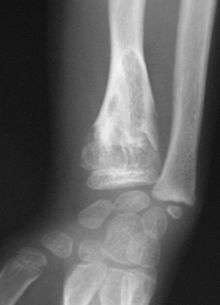

On radiographs, streaks of low density are seen projecting through the diaphyses into the epiphyses of the long bones, due to ectopic cartilage deposits. With age, the cartilage may calcify in the typical "snowflake" pattern.

X-ray showing calcified enchondromas localized in finger a 37-year-old patient affected with Ollier disease